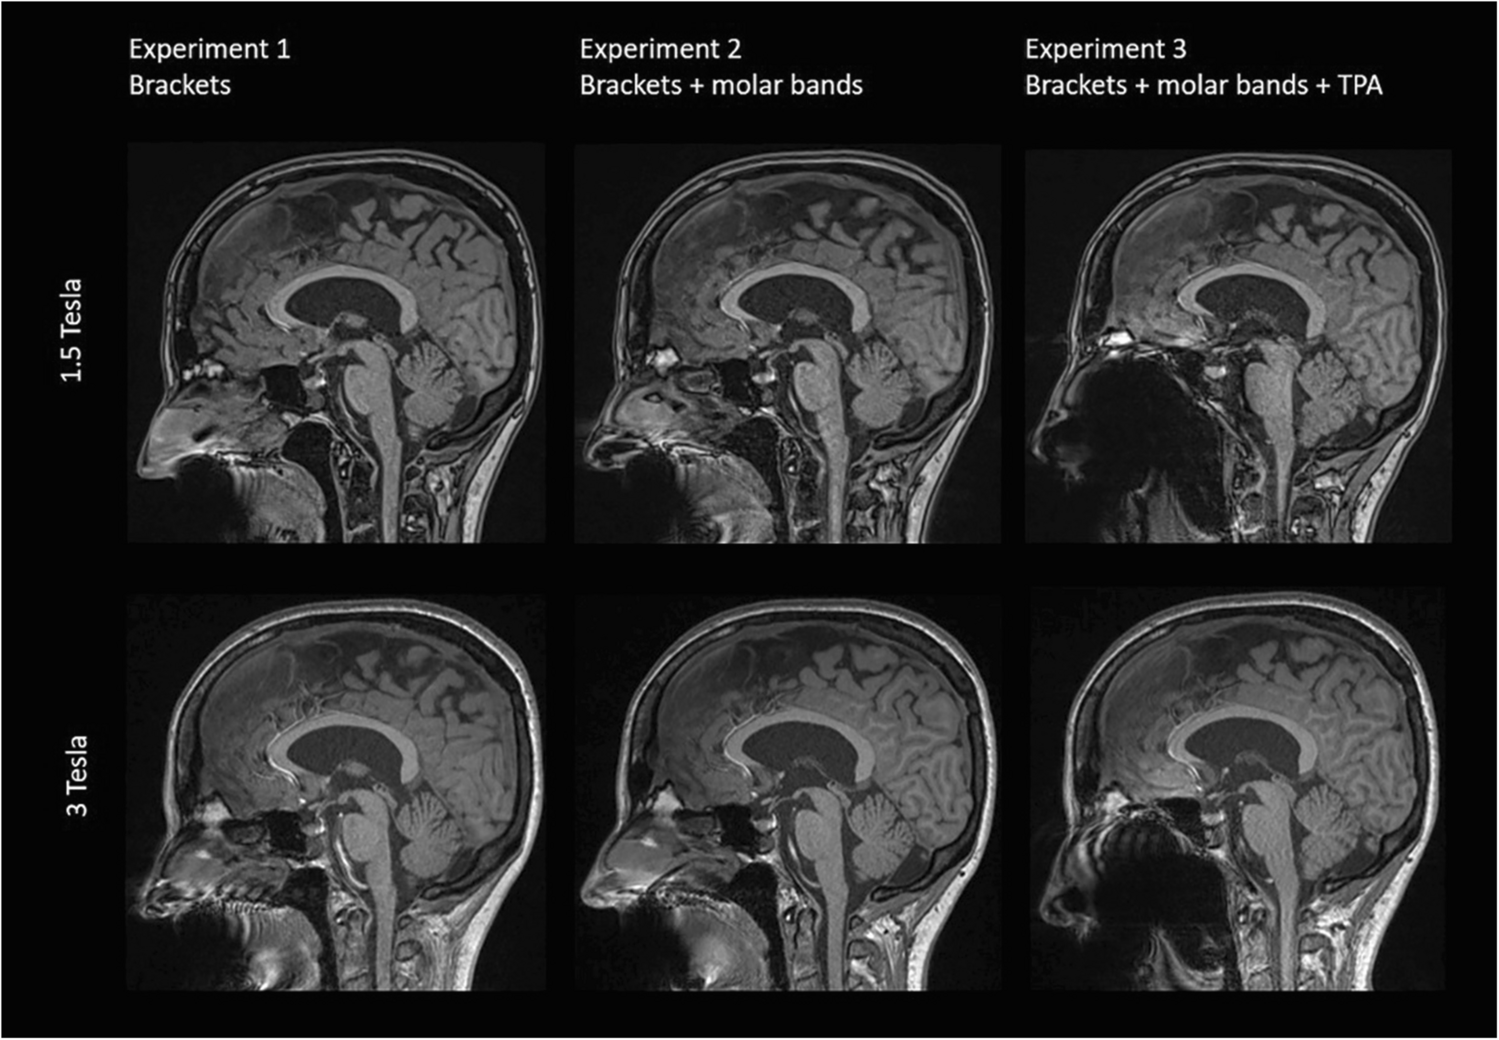

The incorporation of a trans-palatal archwire [Experiment 3] introduced severe artifacts in both 1.5T and 3T imaging, particularly evident in SWI and Diffusion-Weighted Imaging (DWI) sequences, precluding the evaluation of most anatomical structures. Across various sequences, diagnostic quality for facial sinuses was consistently compromised, with maximal artifacts observed in cerebral structures proximal to the skull base (see Tables 2 and 3).

Figure 1 shows representative sagittal T1 weighted images acquired at 1.5T (top row) and 3T (bottom row) for all three experiments. The strongest artefacts occur after introducing supplementary molar bands [Experiment 3].

Fig. 1

Comparison of representative slices of a sagittal T1 weighted image (MPRAGE) from all three volunteer Experiments acquired at 1.5T and 3T

Bild vergrößern